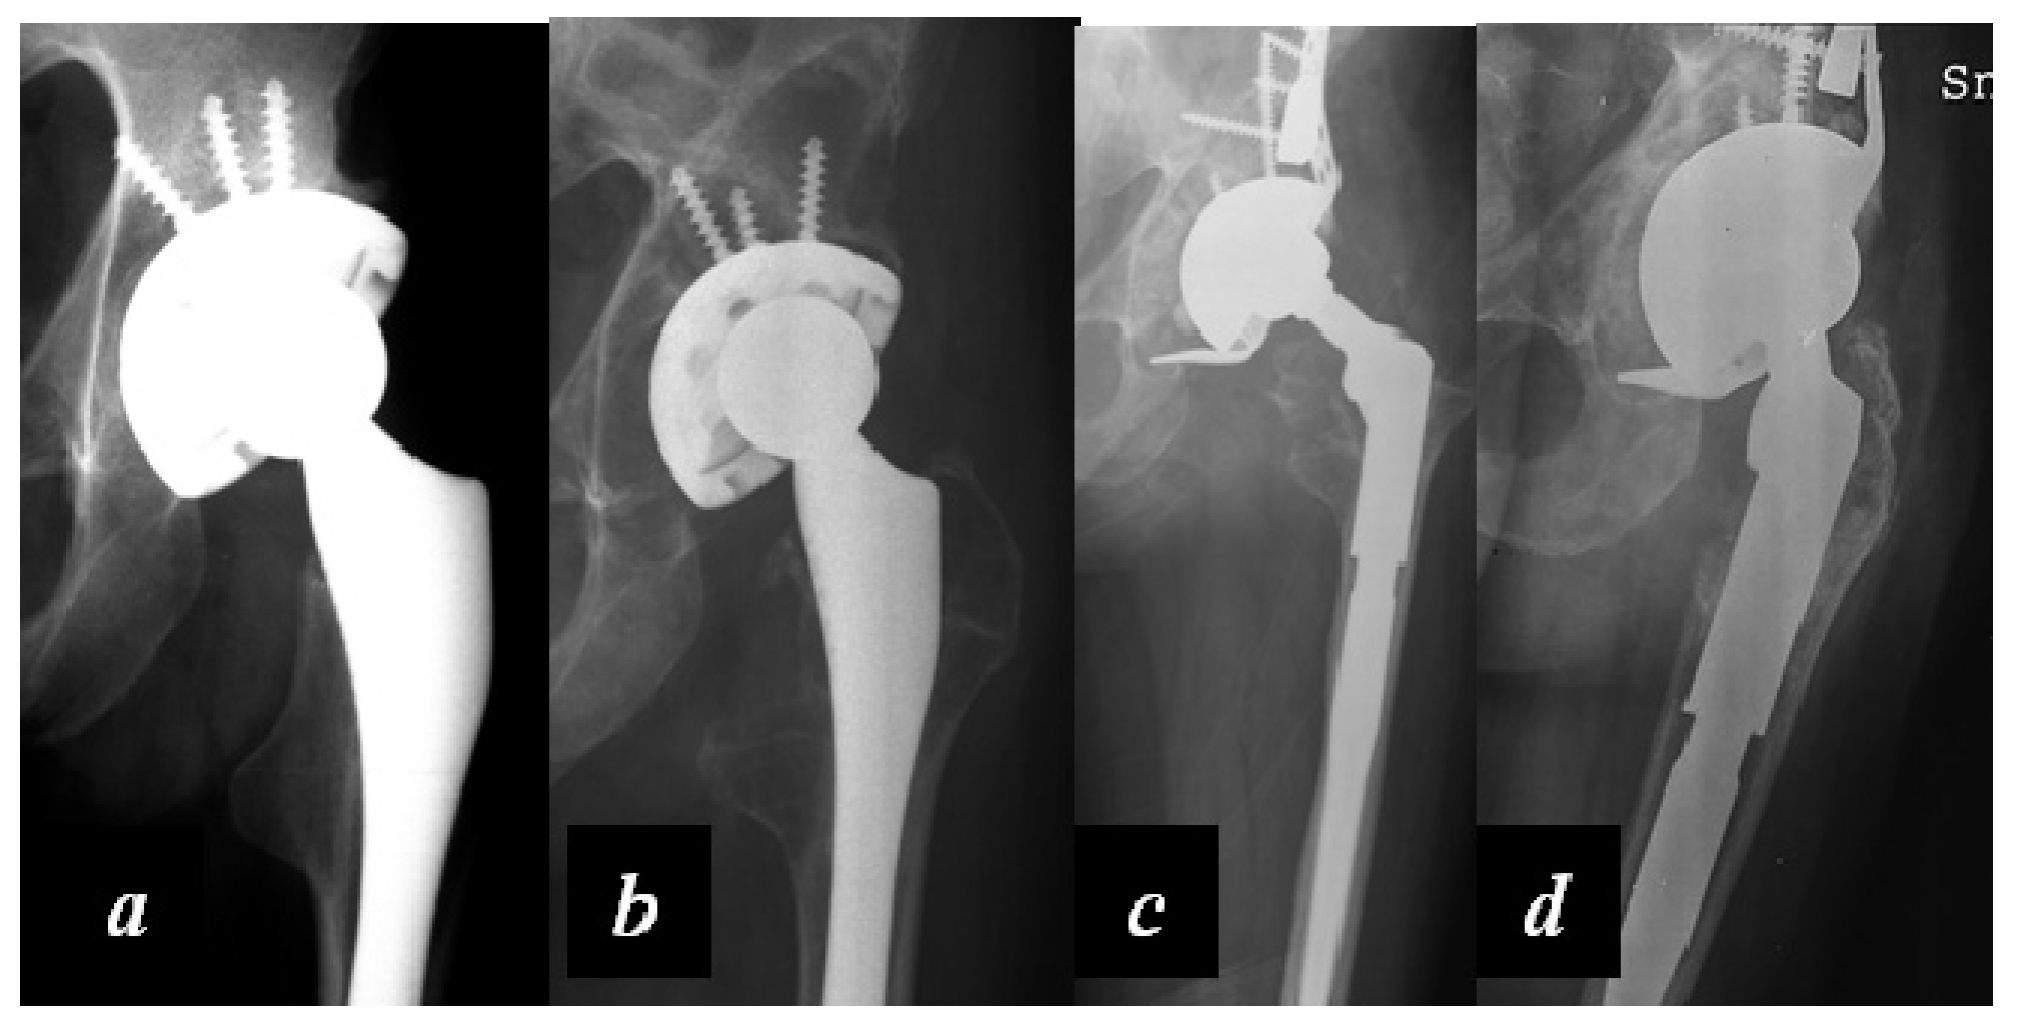

Carulli et al. reported a series of 23 haemophilic patients undergoing THA with modern cementless implants and COP couplings [1]. In 14 subjects, a standard stem was used, while in nine cases a modern short stem was adopted. No failures and no complications were recorded, with a survival rate of 100% at an 8.1-year follow-up (Figure 3 and Figure 4).

Figure 3. (a) Preoperative X-rays of the left hip of a 58-year-old patient affected by severe haemophilia A; (b) Radiographic aspect 6.5 years after surgery: Standard cementless tapered stem with ceramic-on-polyethylene (COP) coupling.

Figure 4. (a) Preoperative x-rays of the left hip of a 33-year-old patient affected by severe haemophilia A; (b) X-rays 3 years after surgery: cementless short stem, acetabular cup fixed with two supplementary screws and COP coupling.